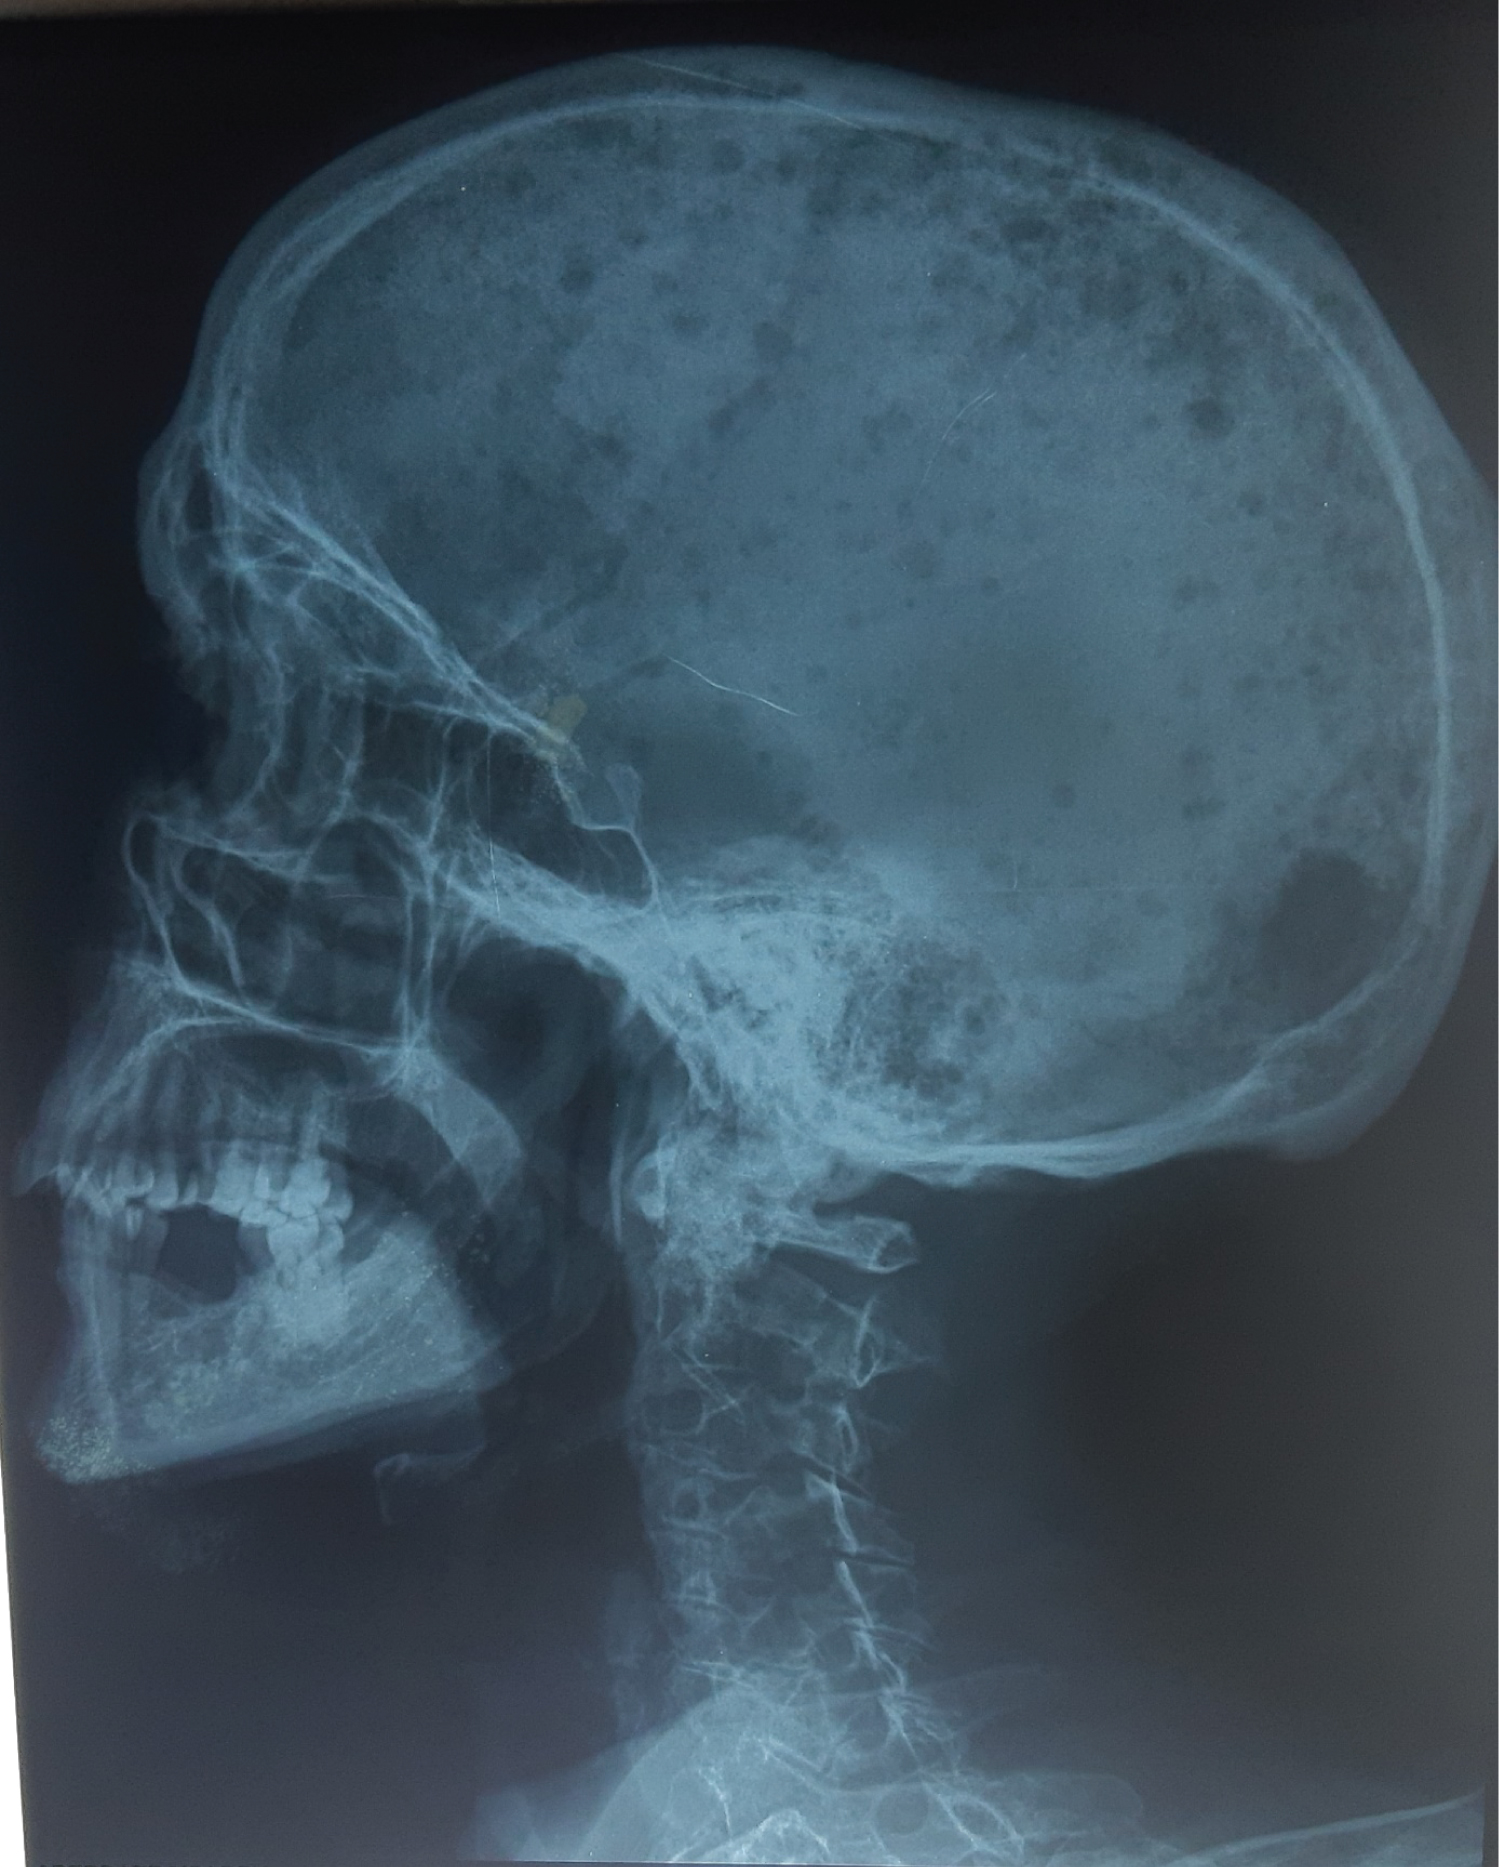

He experienced a back pain, and a weight loss with an average of 20 kg in two months and a fast worsening of the general state. His conjunctivae are discolored. Skeletal X-ray examination detected osteolytic lesions in the skull (Figure 1).

Figure 1: Skull X-Ray. View Figure 1

In IgD MM, the whole skeleton (Spine, Skull, pelvis, ribs...) can be affected by multiple lyric lesions at the diagnosis. Shimamoto, et al. found osteolytic lesions in 42% of patients in their cohort [7], 77% in the cohort of Bladé, et al. and 80% in the cohort of Djidjik, et al. [10].